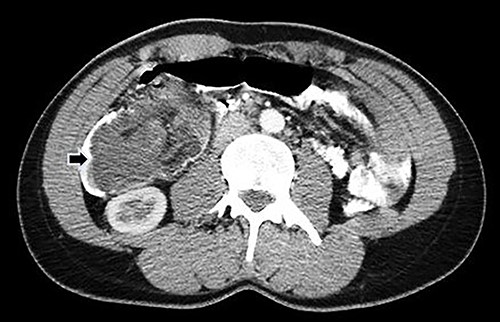

Computed tomography (CT) of the abdomen and pelvis with oral and intravenous contrast was performed (Fig. 1), and emergency surgery was decided due to the suspected ileocolic intussusception with a probable tumor origin (Fig. 2). The preoperative diagnoses were malignant cecum tumor (adenocarcinoma, sarcoma) or benign tumor (lipoma, villous tumor).

Abdominal CT with oral and IV contrast, axial view; tumoral mass and intussusception (arrow).